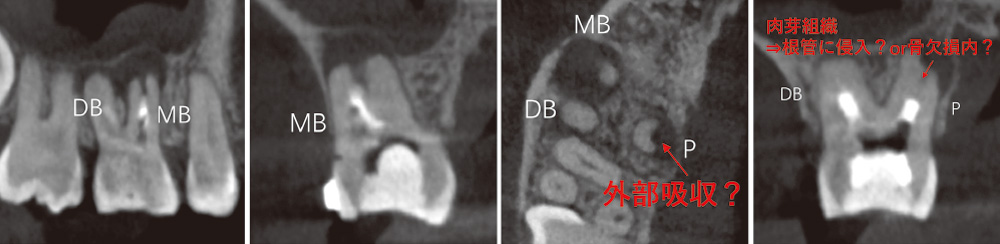

![[写真] CT](/academic/dentalmagazine/wp-content/uploads/sites/2/2025/11/195-3_photo08.jpg)

CTで見ると、近心頰側根も遠心頰側根にも根尖部病変があり、口蓋根は吸収していて、根尖孔が拡大している。この状態になると、根管洗浄を行っても十分細菌が取り切れず、治癒が難しくなる。(Veraviewepocs 3Dfにて撮影) -